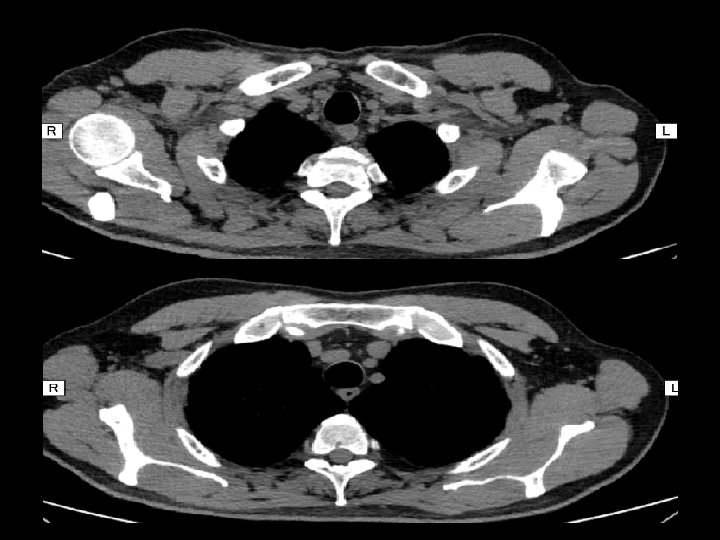

En ambos hemitórax se observan múltiples imágenes nodulillares de escasos milímetros de distribución difusa, predominando en los lóbulos superiores, de localización aleatoria En topografía del LM se observan aisladas prominencias bronquiales con sutiles cambios inflamatorios peribronquiales sin evidencia de consolidación. Pequeñas imágenes ganglionares a nivel supraclavicular en rango no adenopático. En topografía del espacio paratraqueal derecho y espacio subcarinal así como también a nivel hiliar bilateral se observan pequeñas imágenes ganglionares algunas con calcificaciones en su superficie de corte. Derrame pericárdico.

Adenopatías hiliares opacidades nodulares difusas con nódulos más grandes en las zonas pulmonares superiores

Imágenes características en tc: • Pequeños nódulos parenquimatosos distribuidos predominantemente en región peribroncovascular o en septos interlobulillares ( + frec ) • Engrosamiento septal interlobulillar(50%) • Adenopatías mediastinales (39%) • Engrosamiento paredes bronquiales (46%) • Opacidades en vidrio esmerilado (32%) • Patrón en panal de abeja (7%)

Linfoadenopatía hiliar Adenopatía mediastínica